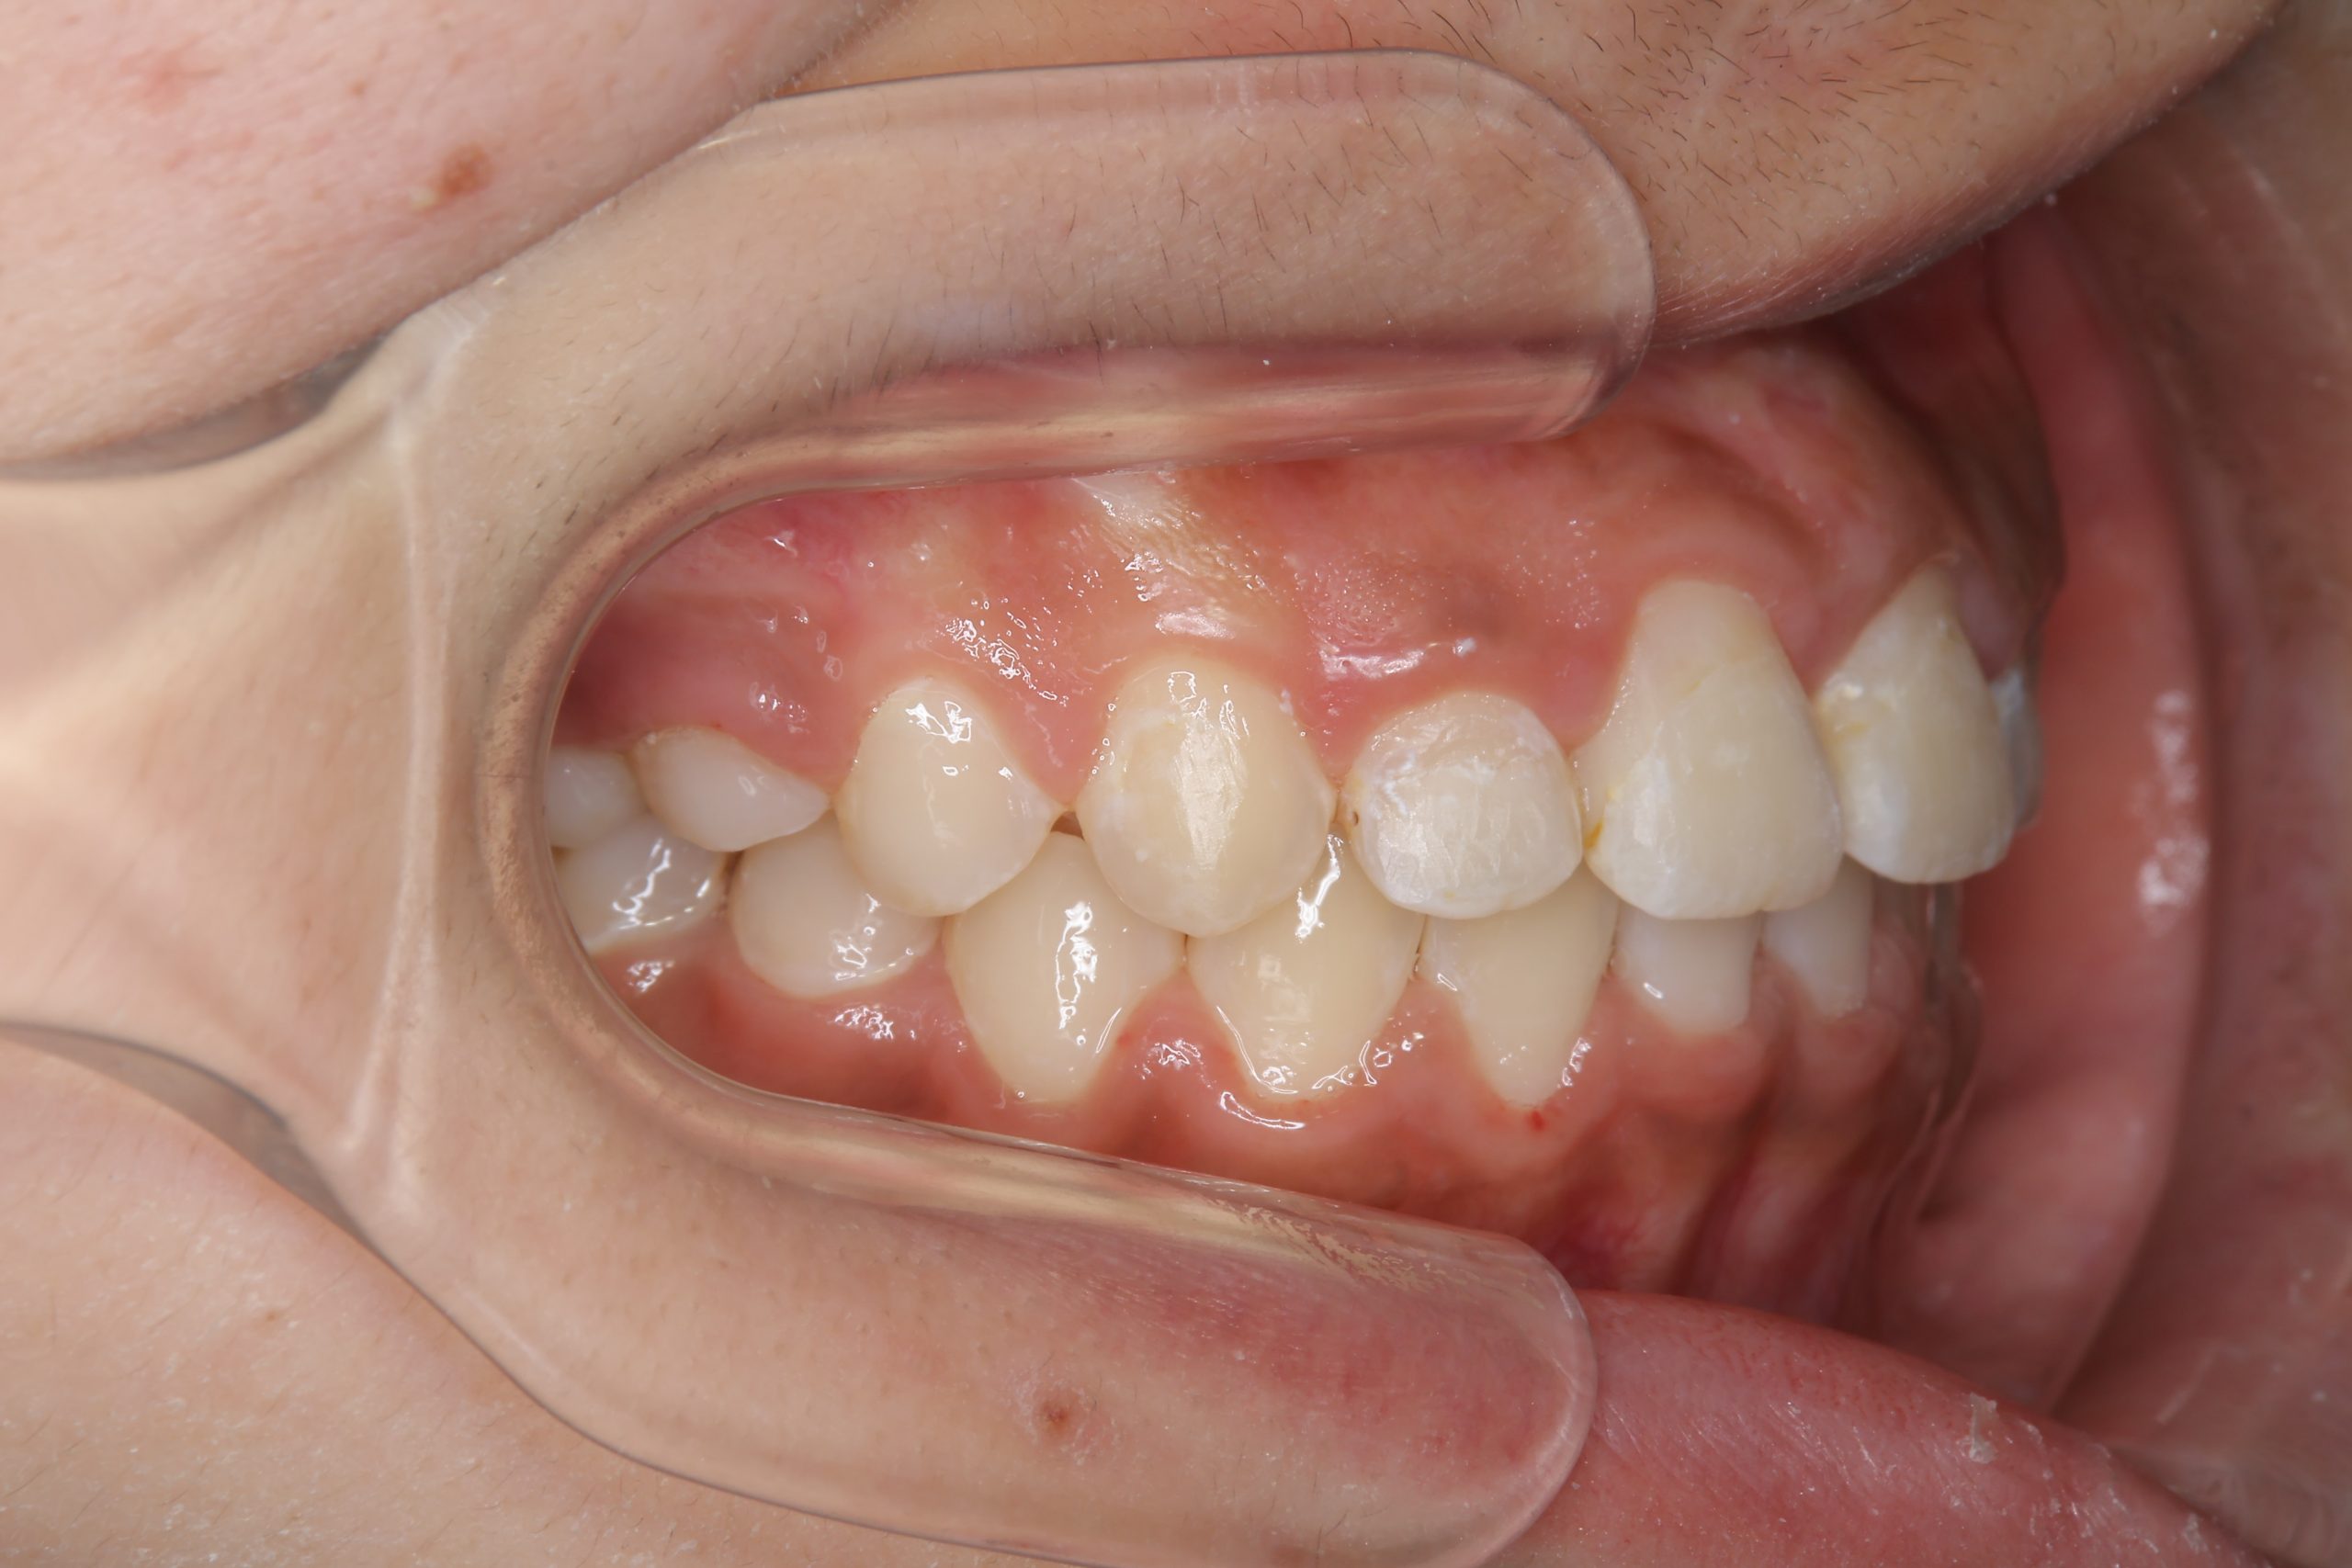

アフター

全顎ワイヤー矯正 症例_474

主訴 歯並びがガタガタで前歯が出ている

施術内容 小児矯正1期治療

治癒期間 1年5か月間

費用 1,020,800円(税込)